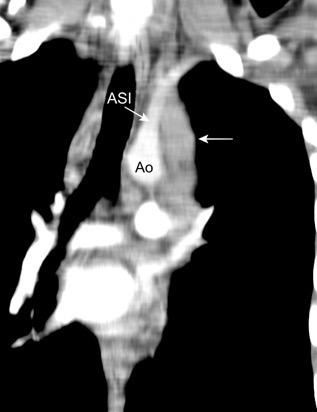

La línea de la arteria subclavia izquierda (ASI) es cóncava en el normal

ASI NORMAL